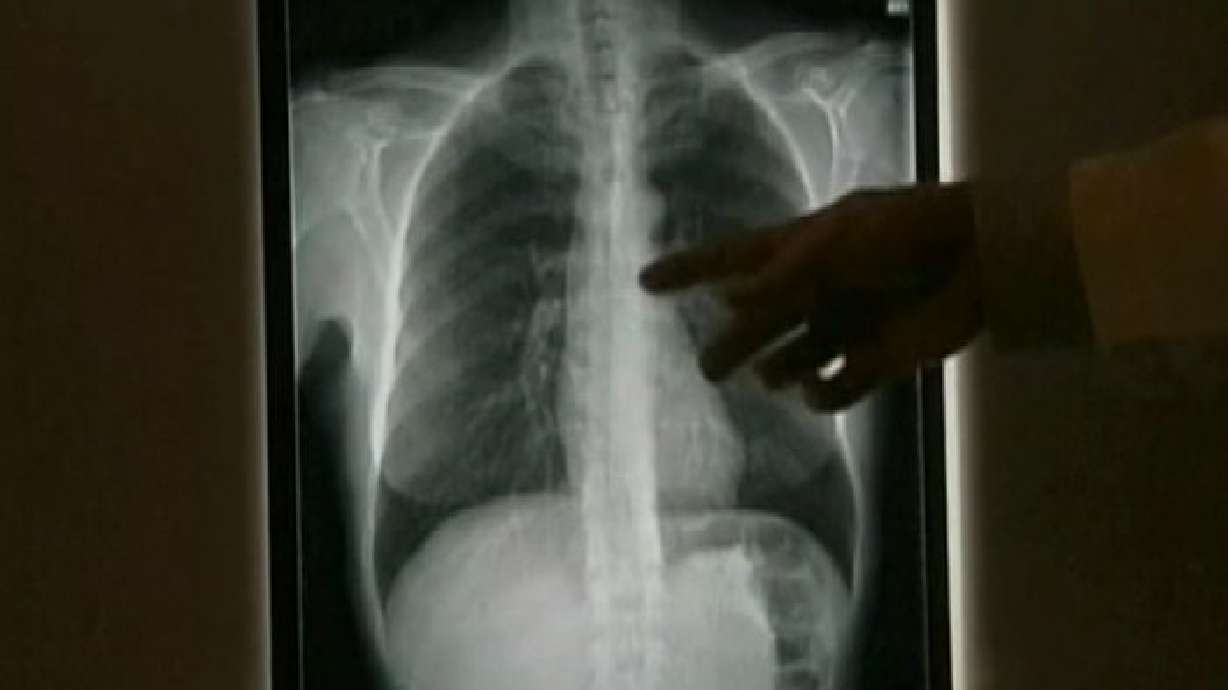

"The chest X-ray came back with a black spot on it, a little smaller than a golf ball," Babineaux said.